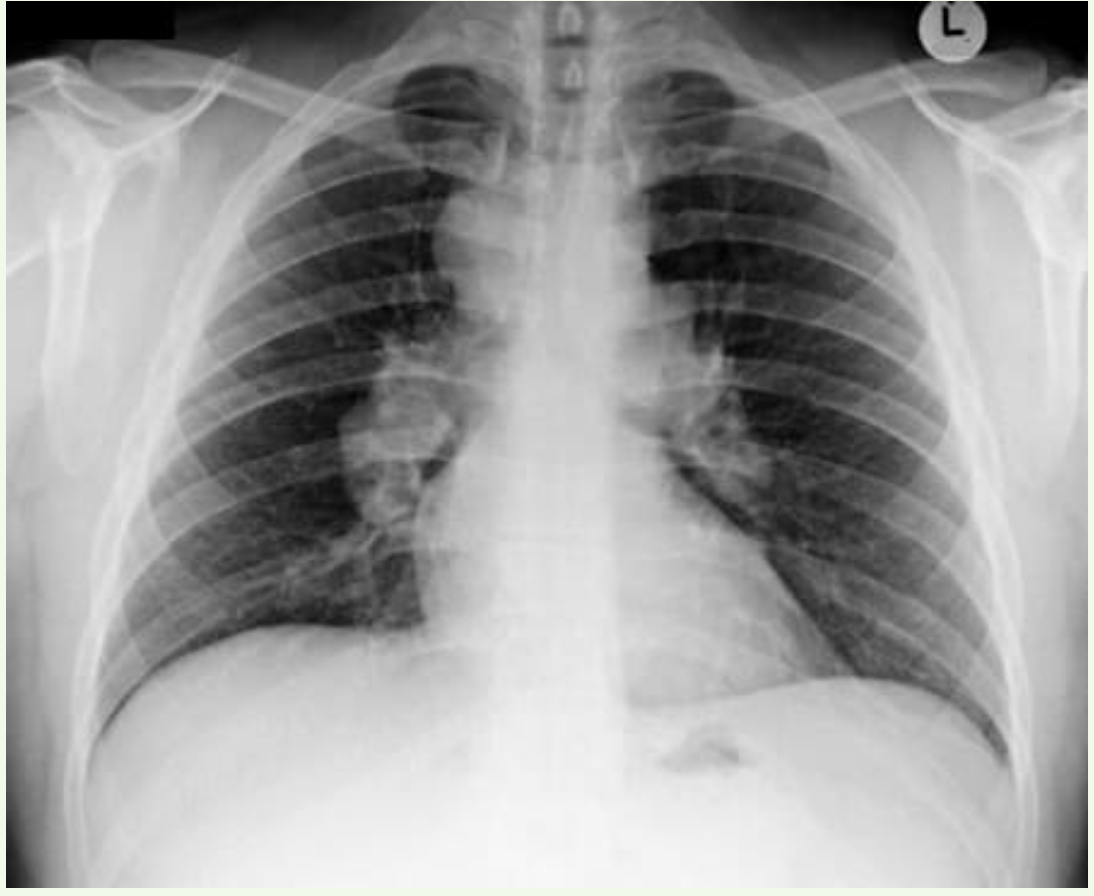

What pathology is shown in this chest x-ray?

• A ) Chronic obstructive pulmonary disease

• B ) Lung cancer

• C ) Normal

• D ) Pleural effusion

• E ) Pneumonia

• F ) Pneumothorax

• G ) Pulmonary oedema

• H ) Tuberculosis

A

Answer: Pulmonary oedema